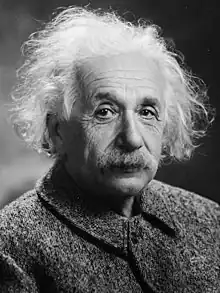

Nissen trained under German physicians Ludwig Aschoff and Ferdinand Sauerbruch. He completed the first pneumonectomy by a Western physician in 1931. In 1948, he performed an abdominal surgery that extended the life of Albert Einstein by several years. Nissen wrote an autobiography published at Deutsche Verlags-Anstalt in 1969 called “Helle Blätter, dunkle Blätter. Erinnerungen eines Chirurgen.“ (ISBN 978-3421014993) which was reviewed in the Journal of the American College of Surgeons.[1] A selection of his writings and lectures was published at Schattauer in 1997 under the title of “Fünfzig Jahre erlebter Chirurgie: Ausgewählte Vorträge und Schriften.“ (ISBN 978-3794506156).

In December 1948, Nissen admitted Albert Einstein to Jewish Hospital for removal of intestinal cysts. However, the scientist was also suffering from an abdominal aortic aneurysm (AAA).[6] An aneurysm is a dilatation that occurs in a blood vessel. In the portion of the aorta that runs through the abdomen, aneurysms are typically asymptomatic until rupture is imminent.[7] AAA rupture can cause immediate death from exsanguination.[8] Definitive surgical treatment for AAA had not been devised in the 1940s. Beginning in 1943, reinforcement with cellophane had been used to induce fibrosis in the vessel, decreasing the risk of rupture. Nissen wrapped the aneurysm with cellophane and Einstein recovered from the surgery.[6]

Upon his hospital discharge, Einstein was surrounded by photographers and he was photographed with his tongue sticking out at them. He sent an autographed newspaper clipping of the photo to Nissen with the inscription "To Nissen my tummy / The world my tongue."[9] Einstein lived for several years after Nissen wrapped his AAA in cellophane.[6] Einstein died in a Princeton, New Jersey hospital in 1955. Initial news reports listed gallbladder inflammation as the cause of death.[10] However, his medical team had suspected gallbladder irritation resulting from a leaking AAA.[11] An autopsy conducted by pathologist Thomas Harvey showed that he died of a leaking AAA.[12]

By the time of Einstein's death, surgical AAA repair was technically possible but still very uncertain.[13] The surgeon who saw Einstein in Princeton, Frank Glenn of New York Hospital, proposed surgery. Einstein was in his seventies and he elected to die peacefully rather than undergo surgery.[6] "I want to go when I want," Einstein told his physicians.[14] He told his secretary Helen Dukas, "I can die without the help of the doctors."[14] He also told her that it was "tasteless to prolong life artificially. I have done my share. It is time to go. I will do it elegantly."[13]